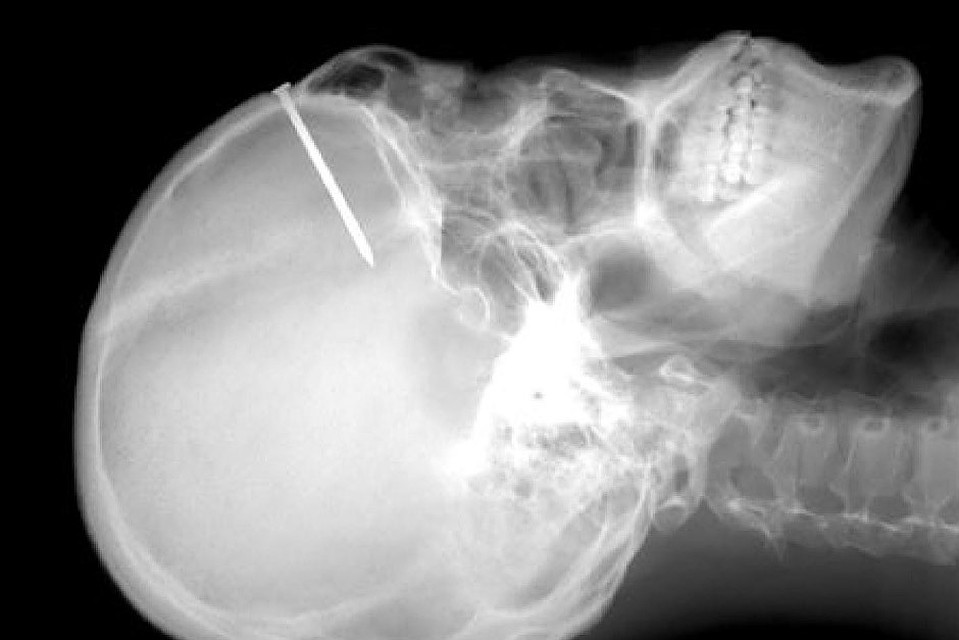

Первый в мире биоассемилирумый гель для регенерации, который позволяет восстановить костную ткань с идентичностью в 100% и лечить, в том числе крупные пулевые и осколочные повреждения костей, разработали специалисты Волгоградского государственного медицинского университета (ВолгГМУ).

Этот препарат представляет собой сложную питательно-строительную смесь, усиленную активаторами регенерации. Такой подход позволяет организму запустить собственный механизм восстановления костной ткани. Материал может использоваться при оперативных вмешательствах на костных тканях челюстно-лицевой области, для заполнения дефектов костной и хрящевой тканей в стоматологии и хирургии»